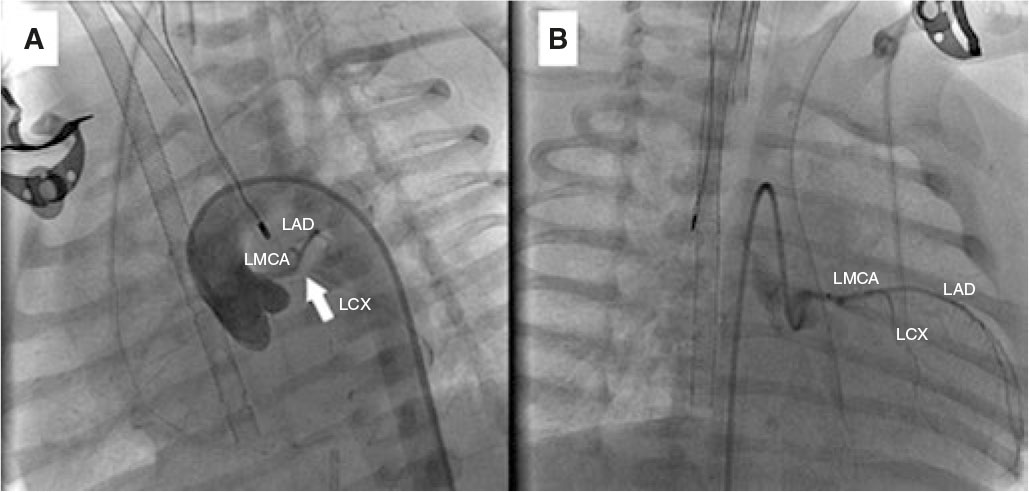

Due to hemodynamic instability despite intubation and vasoactive support, we performed cannulation for extracorporeal membrane oxygenation and cardiac catheterization to rule out coronary artery disease. A normal origin of the left coronary artery was found, with lack of contrast opacification at the junction of the left anterior descending (LAD) and left circumflex (LCX) coronary arteries, and slow distal filling of both vessels (figure 2A and video S3 and video S4; LMCA, left main coronary artery). We performed local fibrinolysis using a microcatheter with administration of 2 boluses of alteplase (0.8 mg and 0.4 mg), achieving recanalization of the LCX and the origin of the LAD (figure 2B).

Figure 2.